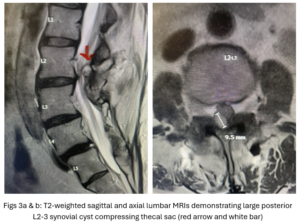

This 50-year-old female with a long history of low back pain and a prior history of multiple lumbar surgeries with instrumentation. She had a L3-5 laminectomy with instrumentation about 7 years prior and now presents with progressive worsening of low back pain. The pain was worse with activity, standing, walking, and prolonged sitting. She had an MRI which showed next segment degeneration at L2-3 with stenosis and the development of a large posteriorly-oriented synovial cyst with thecal sac compression (Fig. 3). The patient failed all means of conservative management including physical therapy and epidurals. We decided to perform an L revision laminectomy to decompress and remove the cyst as well as explore her prior fusion. In this case, again the anterior wall of the sac was completely stuck to the dural membrane. Therefore, we internally decompressed the cyst which was mainly degenerated, necrotic material and removed as much wall of the cyst that could be safely removed. There was some fluid within the cyst. Of note during the dissection of these cysts there is often a release of cyst fluid the patient was well-decompressed. We removed the prior instrumentation and added a new L2-3 construct (Fig. 4). The patient had an uneventful hospital course and was discharged on post op day 2.